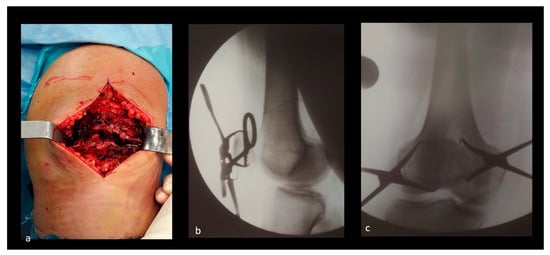

After tourniquet inflation, a midline longitudinal skin incision is performed. The articular surface is accessed through the fracture line and the incision of the retinacula, if needed. The fracture is then reduced using two reduction clamps and checked through appropriate fluoroscopy views (see Figure 1 and Figure 2).

Figure 2.

A clinical case of a transverse patellar fracture. (a) Intraoperative picture. (b,c) X-rays in medio-lateral and antero-posterior views, showing fracture reduction.